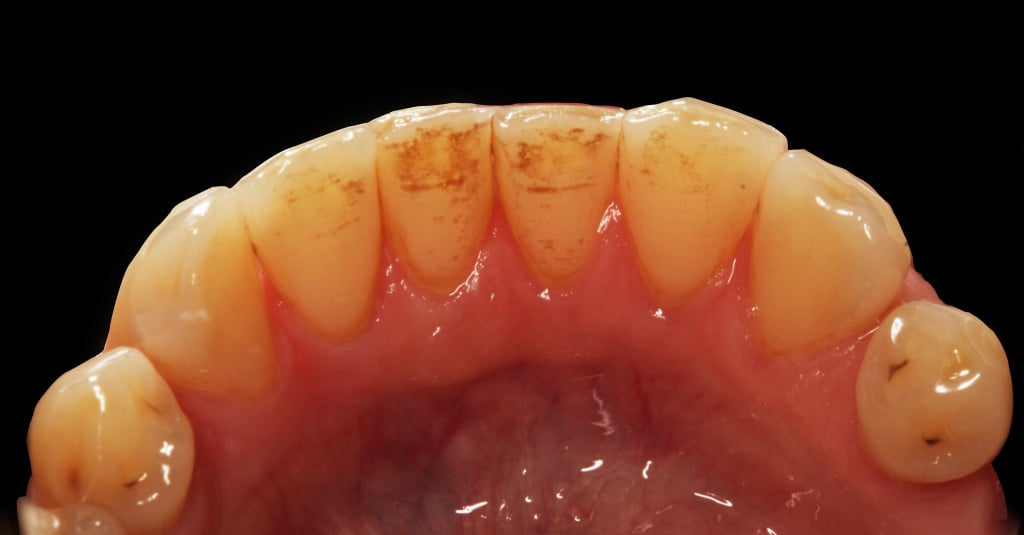

Do kliniki Stomatologia Bez Bólu zgłosiła się pacjentka, lat 61 z problemem nadwrażliwości zębów. Po przeprowadzonym wywiadzie stwierdzono spożywanie sporej ilości sezonowych owoców (truskawki, wiśnie, czereśnie, czarna porzeczka), nawet 3 razy dziennie. Następnie wykonano badanie wewnątrzustne. Stwierdzono obecność płytki nazębnej, ciemnego osadu oraz kamienia nazębnego na części trzonowców: